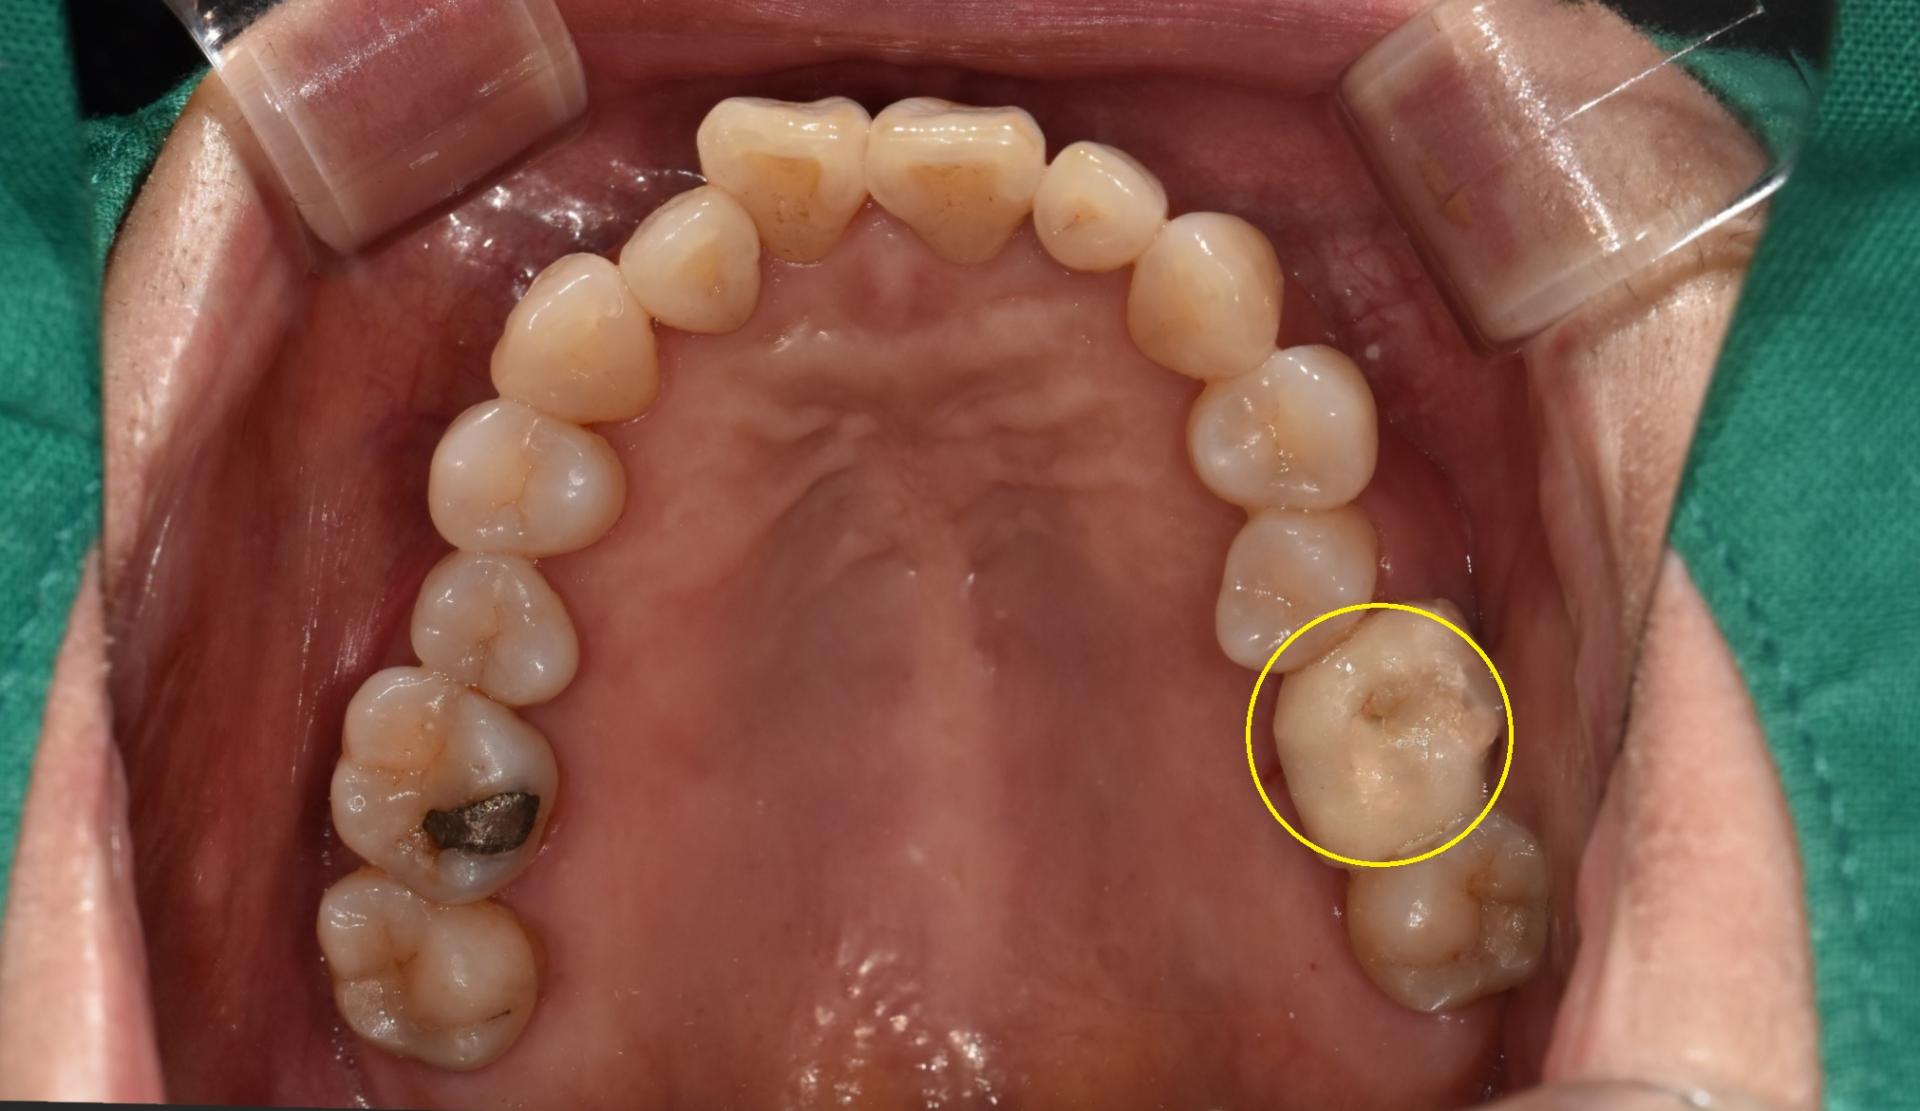

환자분께선 3번의 내원을 통해 신경치료를 마무리하였으며, 노란색 원형 부위를 보면 이전 포스팅에서 말씀드린바, (바로가기) 모든 근관 끝까지 신경 치료용 재료인 Gutta-percha 와 MTA가 잘 채워진 것을 확인하였습니다.